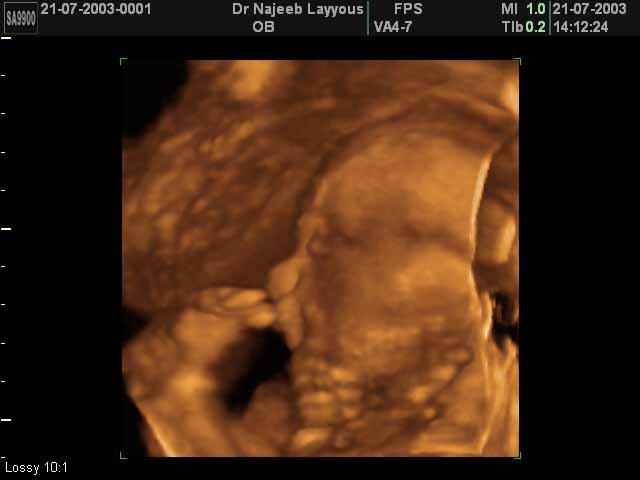

صور جانبية لرأس الجنين بجهاز الالتراساوند ثلاثي الأبعاد | الدكتور نجيب ليوس